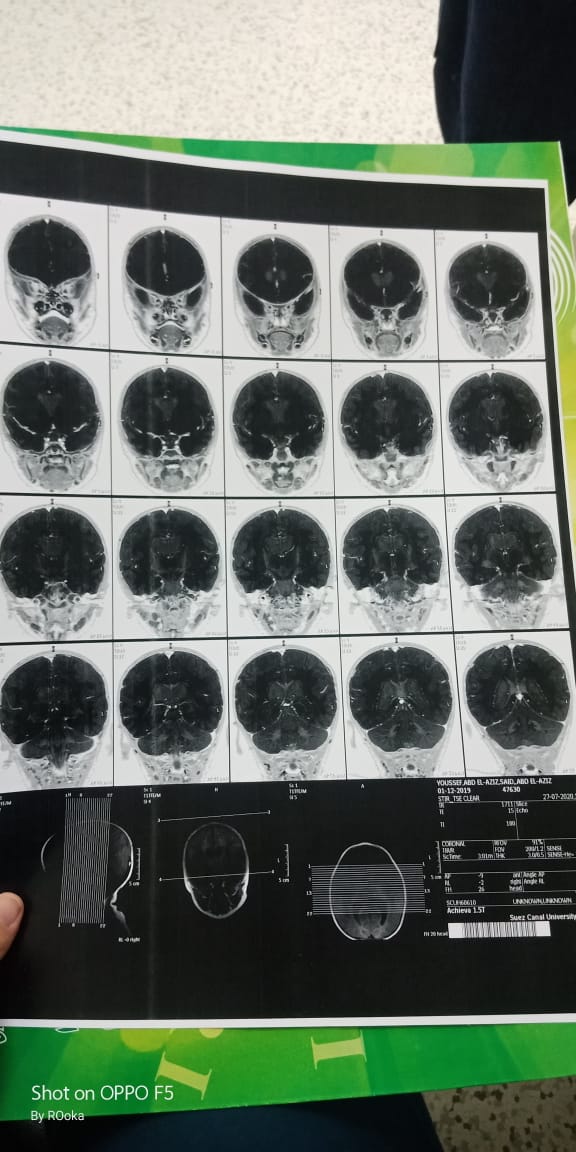

وأضاف عبد العزيز، في تصريحات خاصة لـ القاهرة 24: اكتشفنا مرض يوسف وهو عنده 6 شهور، طلع عنده نقص في المادة البيضاء، ونقص في الأكسجين، مع تآكل في القشرة المخية.

وأكد أن طفله فاقد للحركة والكلام حاليًا، مع تمدد حجم الدماغ، نتيجة معاناته من اختلالات عصبية، التي تنشأ عن المرض، معقبًا: الطفل يحتاج لجهاز طبي يساعد على تخفيف حدة الأعراض، وفقًا لاستشارة الأطباء.